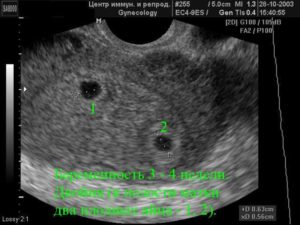

Узи двойни при беременности: фото на ранних сроках в 5-6 недель и позже

Следовательно, наличие двойняшек в утробе выявляется посредством ультразвука уже через месяц после зачатия, на снимке они выглядят как 2 образования темного цвета внутри полости матки (см. фото УЗИ-обследования двойни ниже).

Считается, что точно увидеть несколько эмбрионов, можно только при помощи УЗИ. На каком сроке определяют многоплодную беременность? Специалист может увидеть данный факт в 5-6 недель. Но, как правило, ее диагностируют во время первого скрининга в 12 недель.